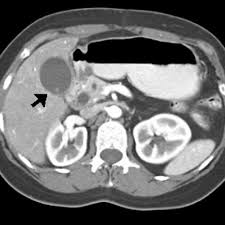

Peutz-Jeghers syndrome is an inherited autosomal- dominant condition characterized by a combination of mucocutaneous pigmentation and multiple small intestinal References polyps 1. Note also subtle enhancing lesions in the liver. A polypoid jejunal mass was demonstrated angiographically.

O seu impacto clínico major em idade pediátrica é resultante das complicações associadas à presença de polipos. However this pigmentation may fade over time Presenting symptoms commonly include GI bleeding abdominal pain or intussusception. Peutz-Jeghers syndrome PJS is caused by changes mutations in the STK11 gene. A Sindrome de Peutz-Jeghers é uma rara condição autosómica dominante caracterizada pela associação de polipose gastrointestinal hamartomas pigmentação mucocutânea e risco acrescido de neoplasias em múltiplos órgãos. 1972-06-01 000000 ABSTRACT-A case of Peutz-Jeghers syndrome is presented. Multiple small and large bowel polyps arrows as well as multiple renal angiomyolipomas in left kidney not normally part of the syndrome. Peutz-Jeghers syndrome PJS is a hereditary cancer syndrome characterized by gastrointestinal GI polyposis mucocutaneous pigmented macules and cancer predisposition. Patients with Peutz-Jeghers syndrome are at an increased risk for developing GI cancers of the colorectal pancreatic and gastri. An increased risk of gastrointestinal and nongastrointestinal cancer.